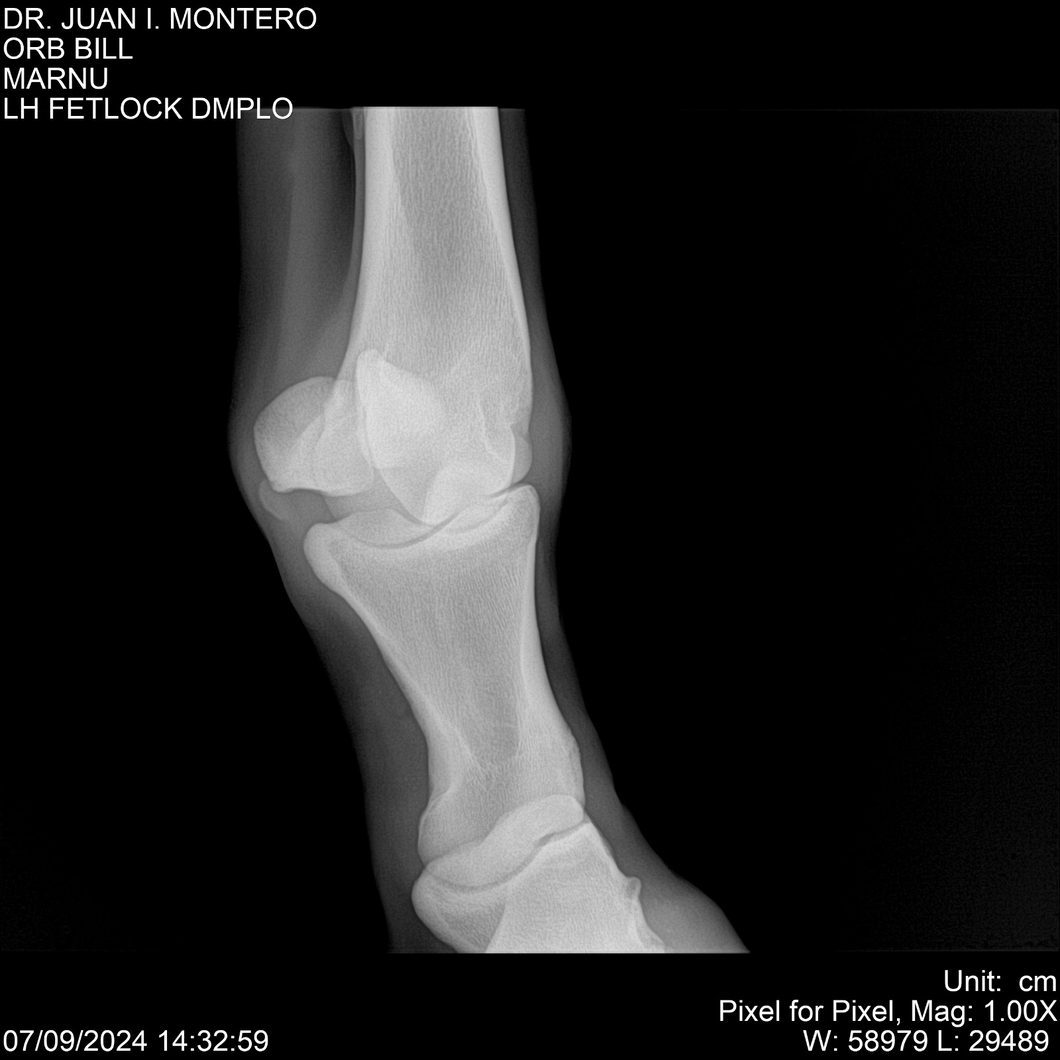

LOTE 7, ORB BILL 🔥 🔥 🔥 Lote Anterior Volver al remate Lote Siguiente Ficha Contacto Montevideo - Ficha del Lote Identificador: #282523 Categoría: Yeguarizos Montevideo - 83 Visualizaciones ClicData Contacto Empresa: Abelenda N. R., Walter Hugo Nombre*: Teléfono* : E-mail* : Mensaje Enviar Registrese gratis Este contenido Exclusivo está disponible sólo para usuarios registrados Ingresar